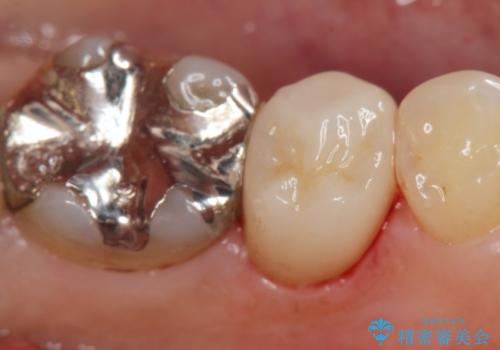

[ 放置し内部で大きく進行した虫歯 ] 神経を守るセラミック治療

担当医 大元洋佑